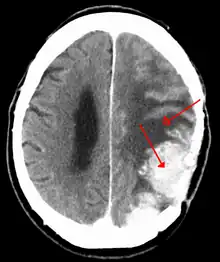

Meningiomas are visualized readily with contrast CT, MRI with gadolinium,[22] and arteriography, all attributed to the fact that meningiomas are extra-axial and vascularized. CSF protein levels are usually found to be elevated when lumbar puncture is used to obtain spinal fluid. On T1-weighted contrast-enhanced MRI, they may show a typical dural tail sign absent in some rare forms of meningiomas.[17]